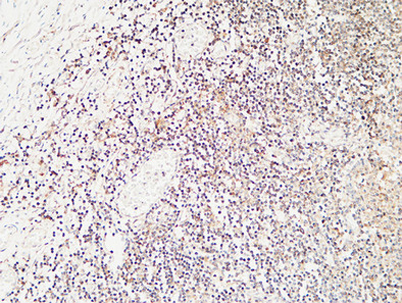

Calcitonin rabbit pAb

Product name: Calcitonin rabbit pAb

Dilutions: IHC-p: 100-300.WB 1:500-2000, ELISA 1:10000-20000

Immunogen: Synthetic peptide from human protein at AA range: 80-141